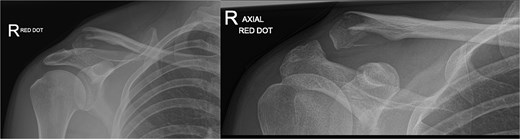

A 15-year-old male sustained a displaced Neer type IV lateral clavicle fracture during a rugby match, presenting with acute pain, deformity, and dorsal displacement without neurovascular compromise (Fig. 1). Imaging confirmed the diagnosis, and open reduction with TightRope and Fiber-wire reinforcement was performed. Early rehabilitation was initiated following short-term immobilization. At 6 weeks, the patient achieved pain-free shoulder function and radiographic stability. By four months, he regained full range of motion and returned to non-contact sports. Minor peri-scar numbness persisted, but imaging confirmed fracture union, and he was cleared for contact activities (Fig. 2A–B).

(A, B) Radiographs showing complete healing of the first case and union at 3 months and 12 months post-operatively.